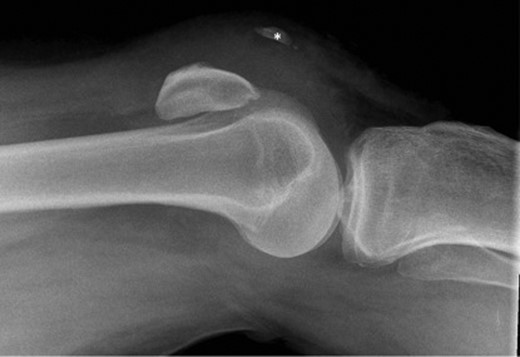

Physical examination showed knee swelling, a high riding patella with a palpable gap below the patella. The patient was unable to weight bear and could not perform active knee extension on his right knee. There was no obvious laceration or injury to the knee. Neurovascular examination was normal. Apart from ectopic ossification of the patellar tendon, plain radiograph showed no evidence of acute fracture or joint effusion (Fig. 1). Because of the unusual mechanism of injury and the initial ultrasound performed in A&E which suggested a rupture of the quadriceps and patella tendon, magnetic resonance imaging (MRI) was performed and demonstrated complete rupture of the patellar tendon from the inferior pole of patella, an almost complete shearing of quadriceps tendon off the patella and chronic tendinosis in the mid-portion of patellar tendon (Fig. 2).

Lateral radiograph of right knee, demonstrating patella alta and ectopic ossification of the patellar tendon (marked *). No evidence of acute fracture.